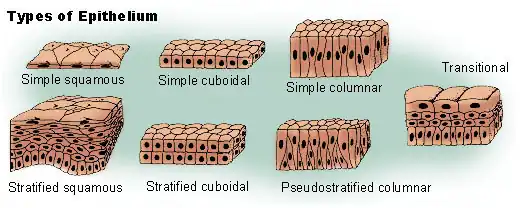

Histologists classify epithelia cells by appearence. Single layer epithelias is called 'simple'; multilayer is called stratified. The diagram below shows a typical histological classification. Plain light microscope appearances appear in the thumbnails to the right.

Histological classification of Epithelia

As physiologists we find it more useful to classify epithelia by function: